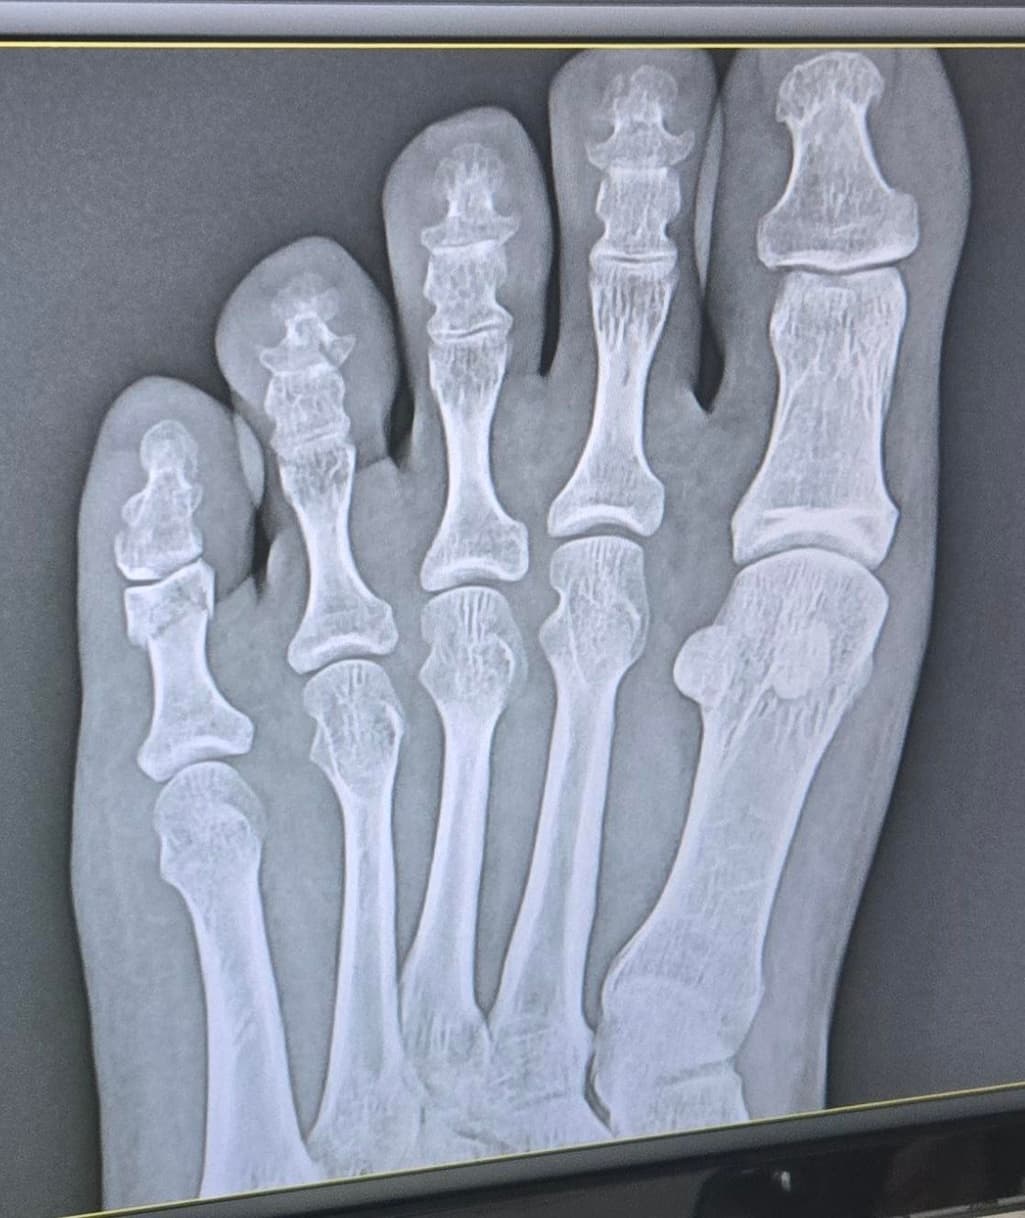

오늘 다른 병원에서 찍은 엑스레이 사진이고 테이핑만 하고 6주 정도는 봐야된다고 하셨어요

Q. 제 상태가 어떤 상태인지 자세히 알고 싶어요. 금 갔다고 하셨는데 측면 사진에서 어긋난 보이는 건 뭔지 특히 궁금합니다!(의사선생님께 자세히 못 여쭈어봐서..ㅜㅜ)

새낄 발가락 골절은 보통 뼈가 크게 벌어지지 않은 금 간 상태라면 수술은 꼭 필요하지 않을 수 있습니다. 또한 엑스레이에서 어긋나 보이는 건 충격으로 미세한 틀어짐인데, 의사 선생님이 수술은 필요 없다고 한 건 기능에 문제 없는 정도라고 판단하신 것 같습니다.

X-ray에서 보이는 어긋난 부분은 골절 부위의 미세한 변위로, 금이 가면서 뼈 조각이 살짝 벌어진 싱태일 수 있습니다.

원래 뼈구조이며, 발가락 뼈의 측면을 촬영한 것으로 보입니다.

우선 현재 사진만으론 엑스레이를 확인 할 수 없지만 측면에서 어긋난것으로 보여집니다.